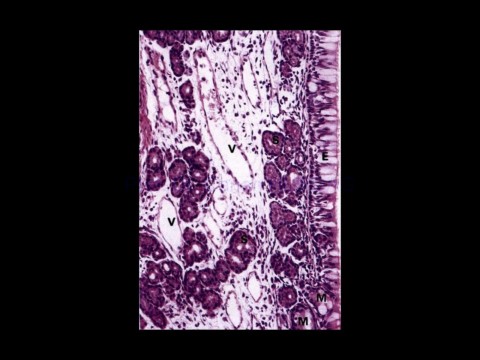

Page 35 - Solunum Sistemi

02-Dec-20                                     Solunum sistemi histolojisi,                                                 35